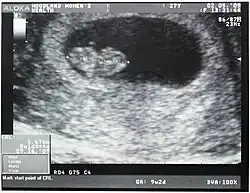

Longitud céfalo-caudal

Longitud céfalo-caudal (o CRL del inglés crown-rump length) se puede encontrar en textos con el nombre de Longitud Coronilla-rabadilla, longitud vértex-cóccix, es la medida de la longitud de embriones y fetos humanos entre la coronilla y la rabadilla. Normalmente se determina mediante ecografía. Se puede utilizar para estimar la edad gestacional (transcurso de tiempo desde el primer día del último período menstrual).

Los embriones y fetos flotan en el líquido amniótico dentro del útero de la madre. Comúnmente forman una curva semejante a una C. Si el cuerpo del feto está estirado (recto), la longitud puede variar ligeramente. La medición se ha de realizar en el estado natural, con el cuerpo curvado. Esta cuantificación es útil para determinar la edad gestacional y la correspondiente fecha del parto.